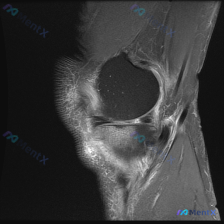

看到这个很有代表性的读片病例,整理出来和大家分享,这个临床-影像不匹配的情况其实临床工作中挺常见的。 病例基本信息 本次分析基于一张膝关节矢状位T1加权磁共振图像,临床提示存在「chondral abnormality(软骨异常)」,无其他病史、体征或检验结果提供。 影像基本观察(单张T1序列) 先...